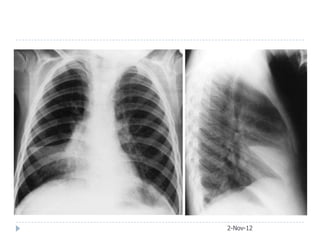

Case 5  65-year-old female presented with acute respiratory failure. She had been sick for two weeks with fever, confusion, diarrhea, cough, and purulent sputum production. Her medical checkup two months ago was unremarkable.  Urea 11 mmol/L, Creatinine 3.2  CXR and later CT chest obtained 2-Nov-12

• #20 PA film showing consolidated right upper lobe. Lateral film showing consolidation limited inferiorly by horizontal fissure (arrows).

• #32 Legionella

• #33 A, Legionellosis, initial chest radiograph showing left lower lobe consolidation.B, Legionellosis, initial chest computed tomography demonstrates left lower lobe alveolar infiltrate and pleural effusion.